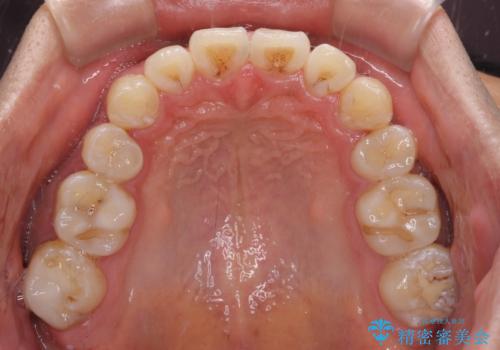

前歯の叢生を解消 ワイヤー装置での抜歯矯正

- 前歯の叢生と八重歯を気にして来院された患者様です。

叢生が強く、奥歯の咬合も左右差が大きかったため、上下左右4本を抜歯して、ワイヤー矯正を行うこととしました。